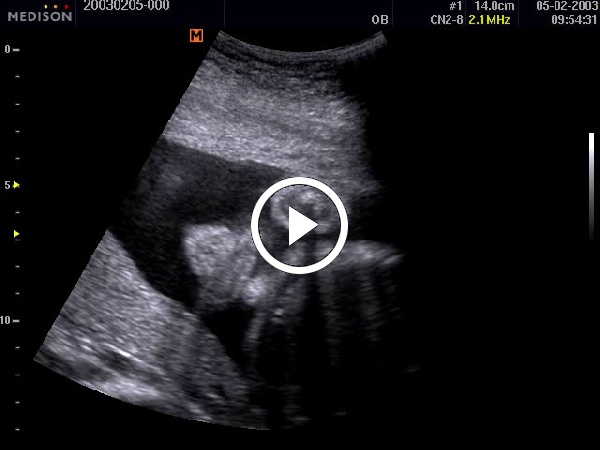

1. B-mód (2D -mód) Cine képei